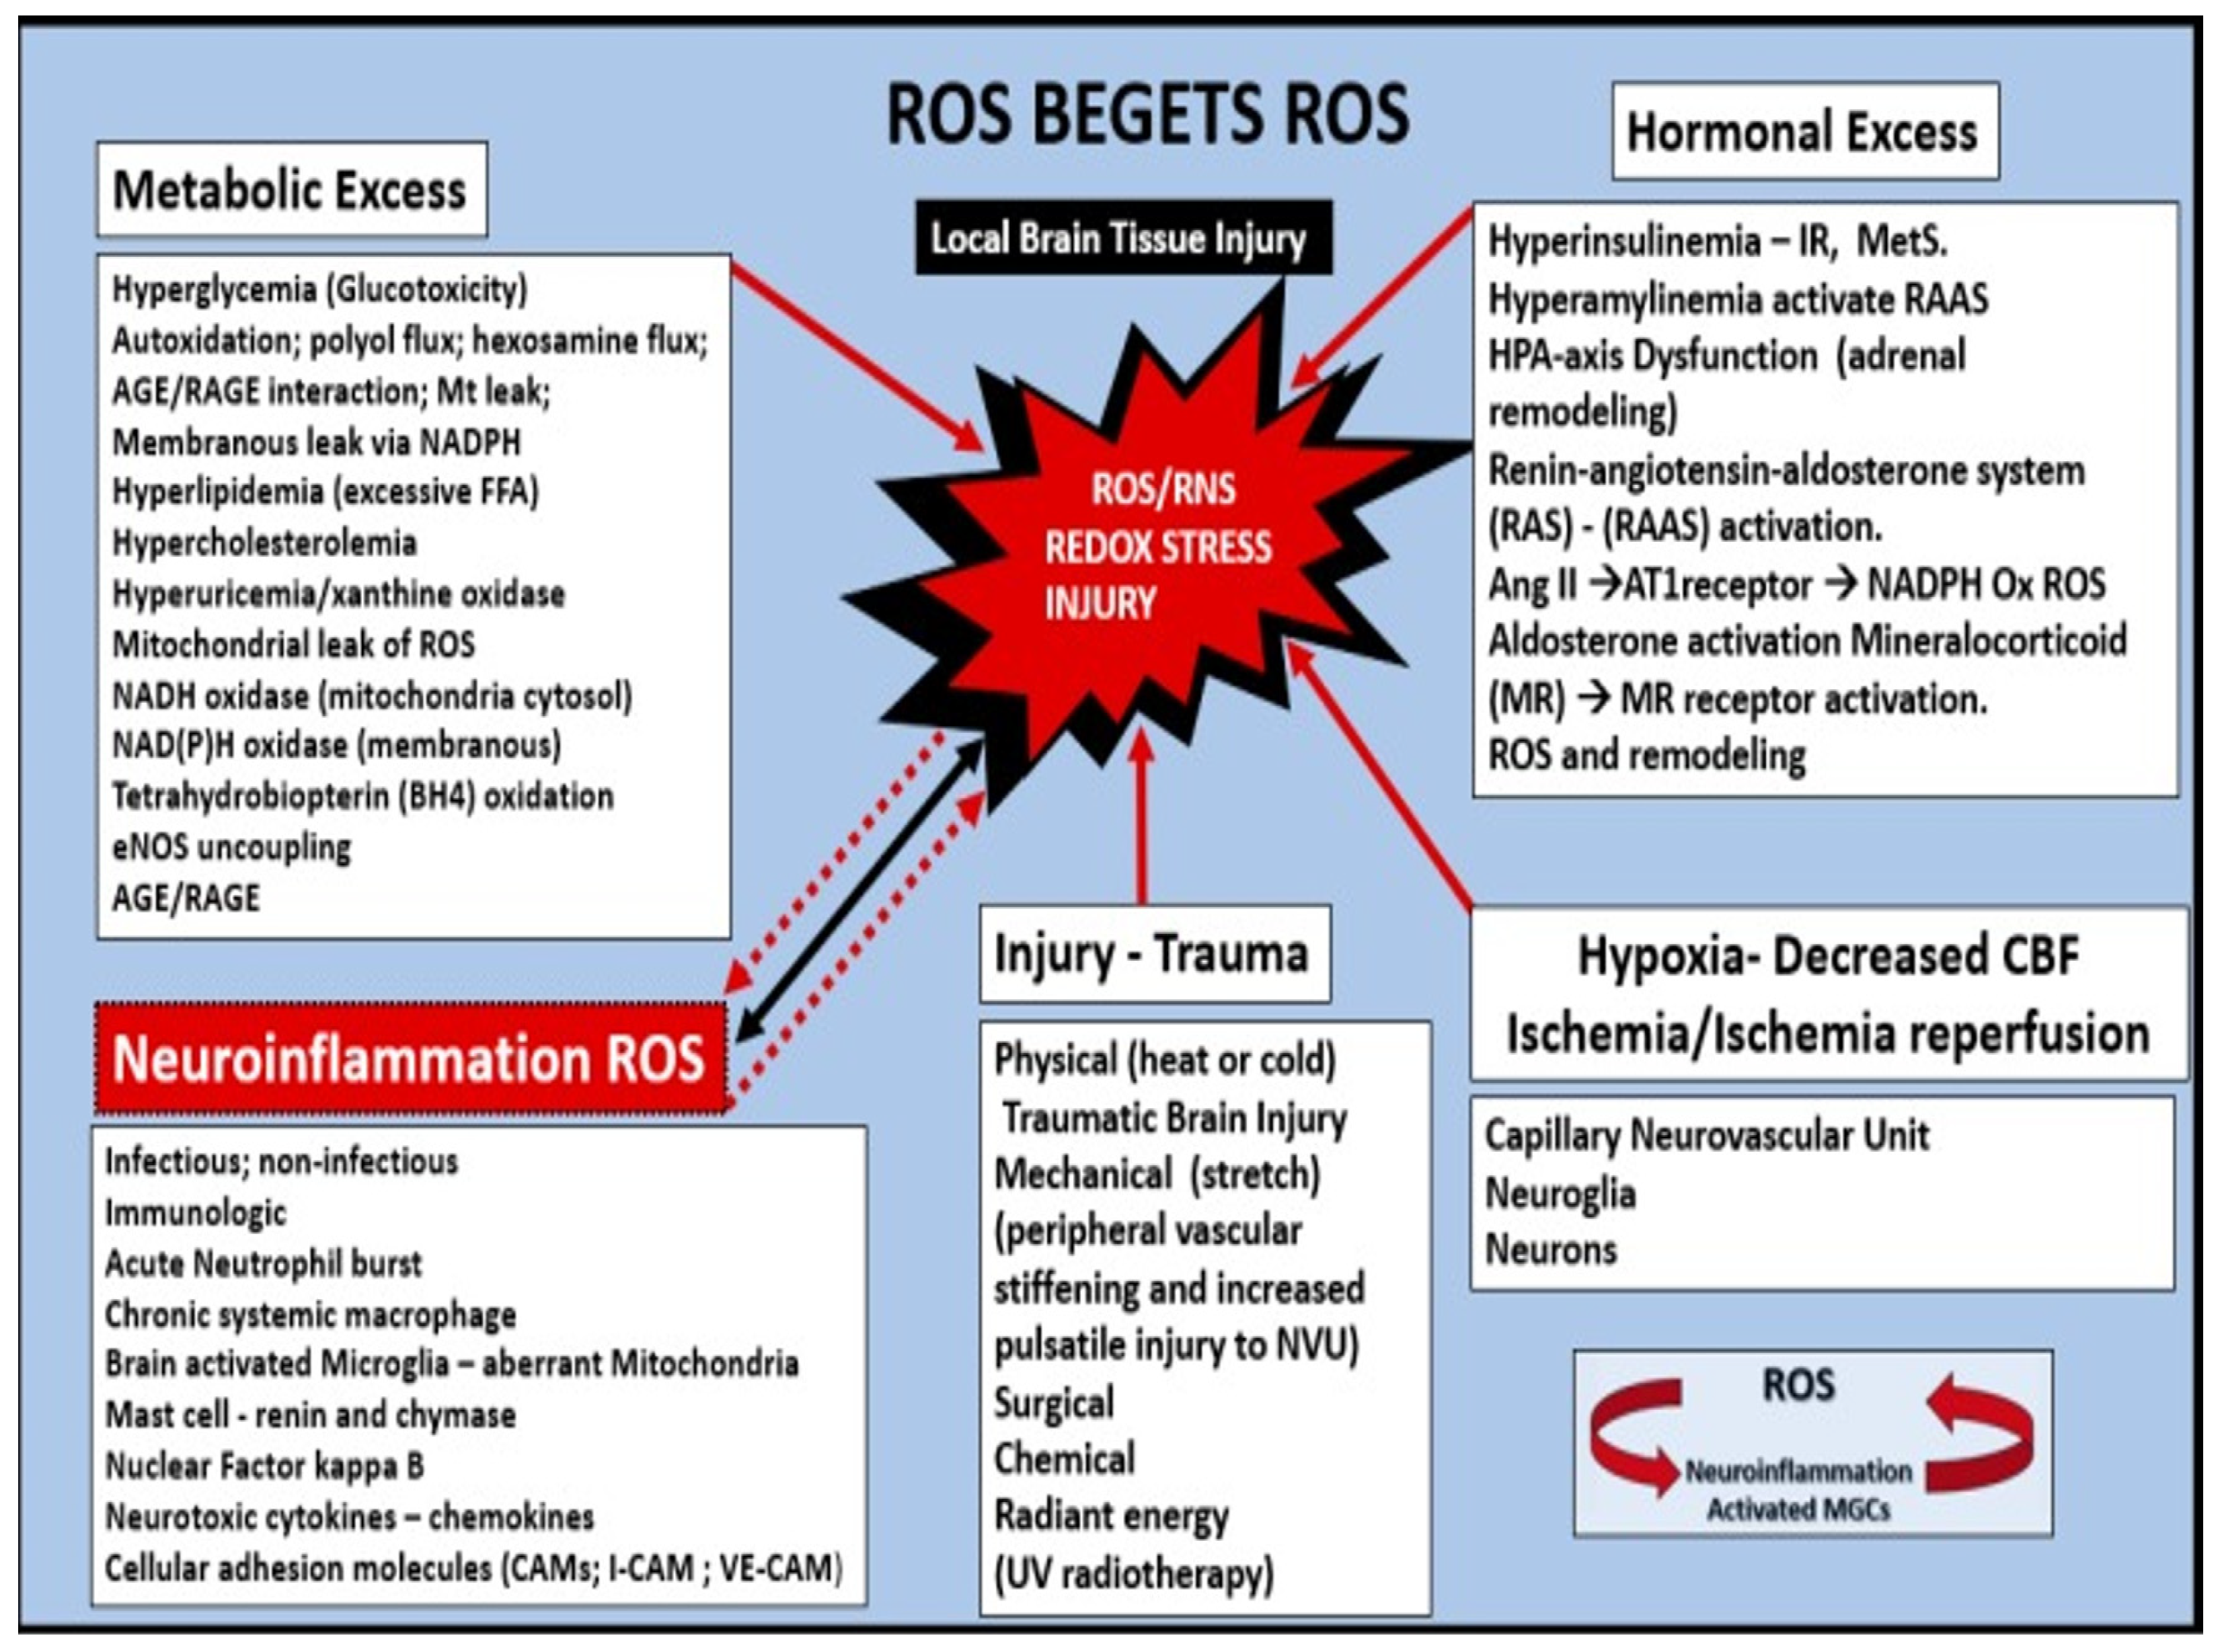

Oxidative—Redox Stress: Implications in the Development of CAA, LOAD, SVD, and CMBs